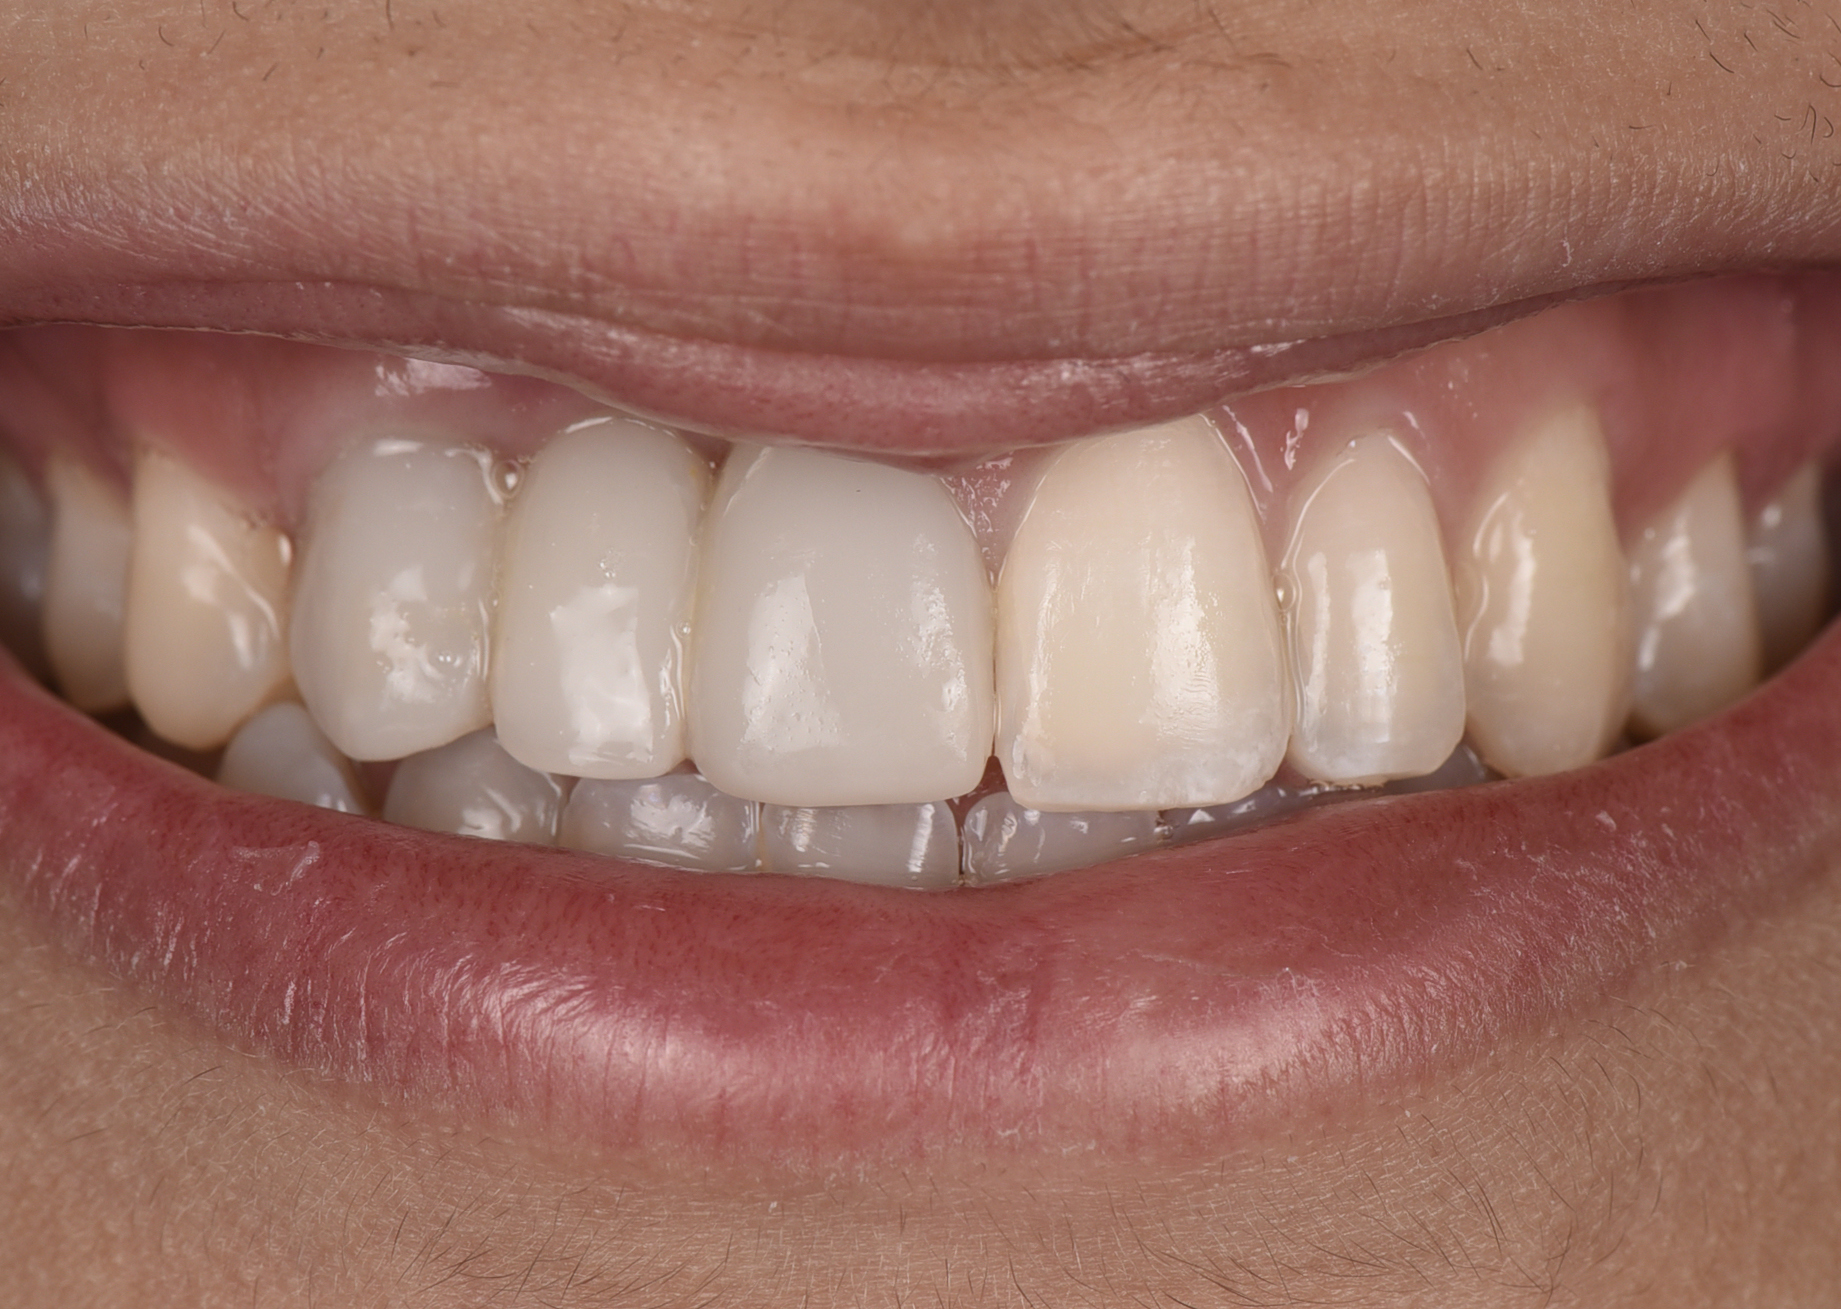

A healthy 20-year-old woman presented to the author’s office requesting treatment for a large defect in the area of missing tooth No. 7. She exhibited a high smile line that revealed a clearly visible deformity, associated with pain and sensitivity on teeth Nos. 6 and 8 and in the area of tooth No. 7 (Figure 1). Although the patient wore a modified Essix retainer, the defect was still visible because of the magnitude of tissue loss and the revealing nature of her smile.